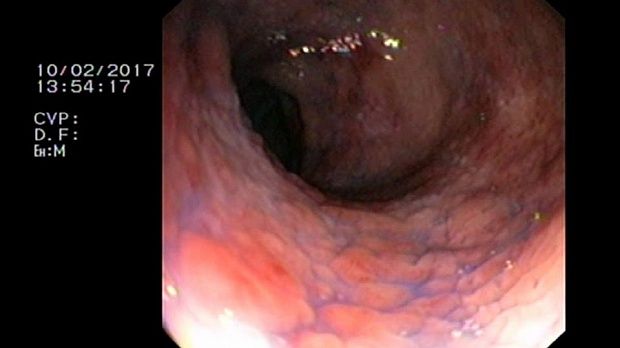

- Атлас